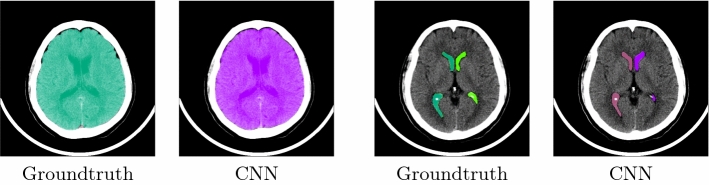

Fig. 2.

Automatic segmentation results for brain volume (left) and ventricles (right). The first and third images show the ground truth masks, whereas the second and fourth display the automatically generated masks

The segmentation task was tested on a data set of 22 volumes that were excluded from the CNN training. The corresponding results are presented in Table 1. The segmentation method for the brain volume achieves the highest Dice coefficient of 0.97, whereas the segmentation of the ventricles leads to a Dice of 0.89. The high Hausdorff values are especially due to the fact that parts of other nearby structures are wrongly assigned. In particular, for the very small 4th ventricle, parts of the LLV and RLV are misidentified as part of the 4th ventricle. Figure 2 shows exemplary results for a test case. Moreover, Fig. 3 displays the qualitative results on two cases with disease, in which the brain volume and the ventricles are automatically segmented.